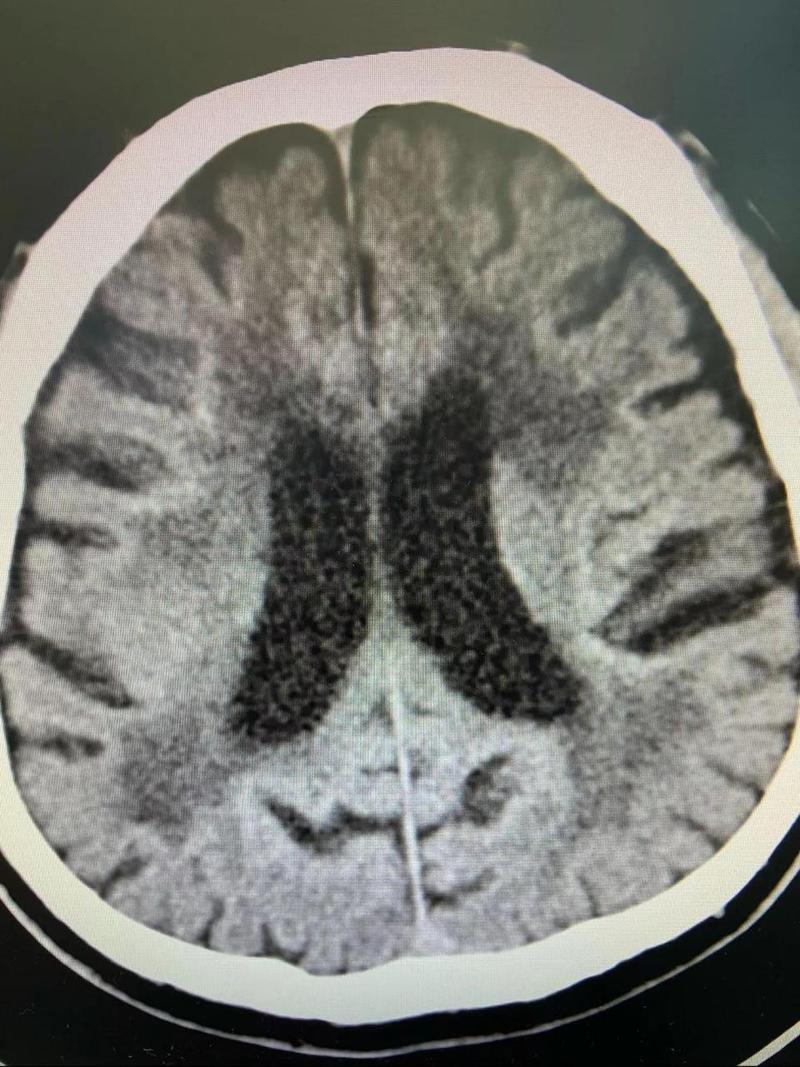

(图片来源网络,侵删)

(图片来源网络,侵删)- 糖尿病、高脂血症:会加速全身血管的动脉粥样硬化,包括脑小血管。